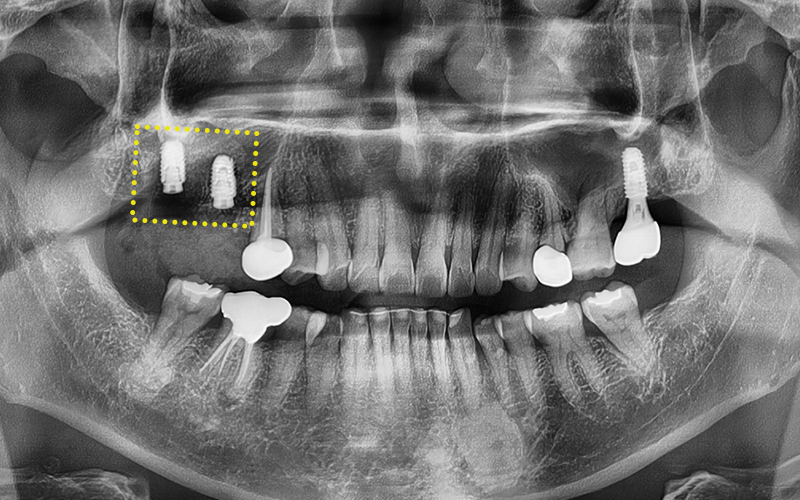

식립 후 한달체크때

별다른 이상이 없는것을 확인해주었고

임플란트가 잇몸뼈에 잘 유착될동안

기다려주기로 하였습니다.

✅ 2차 수술 완료

임플란트가 잇몸뼈에 잘 유착된것을 확인하고

2차 수술을 진행해주었고,

본뜨기 작업을 시행 후, (왼쪽 사진)

맞춤형 지대주를

체결해주답니다. (오른쪽 사진)

이제 보철물만 올리면

치료는 마무리 됩니다!